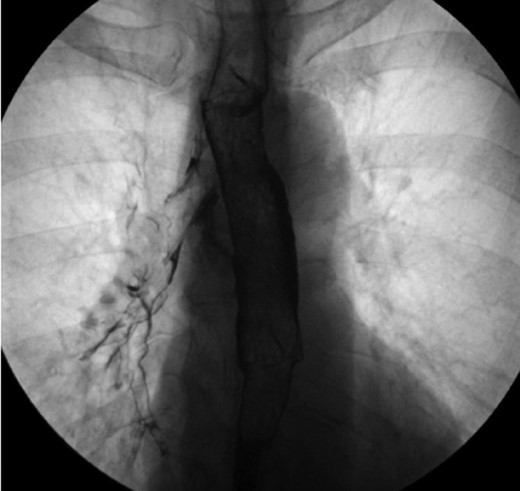

One-year after her original presentation, the patient presented to the emergency room with worsening cough and choking with oral intake. A CT scan of chest revealed a fistula between the right mainstem bronchus and esophagus (Fig. 2A). The patient underwent rigid bronchoscopy revealing a 2-cm defect on the medial wall of the right mainstem bronchus, ~1-cm from the main carina (Fig. 2B). A CT esophagram confirmed extravasation of oral contrast into the tracheobronchial tree (Fig. 3).

(A) CT scan revealing fistula between the right mainstem bronchus and esophagus. (B) Endobronchial view visualizing right mainstem defect.

Esophagram revealing extravasation into the tracheobronchial tree.